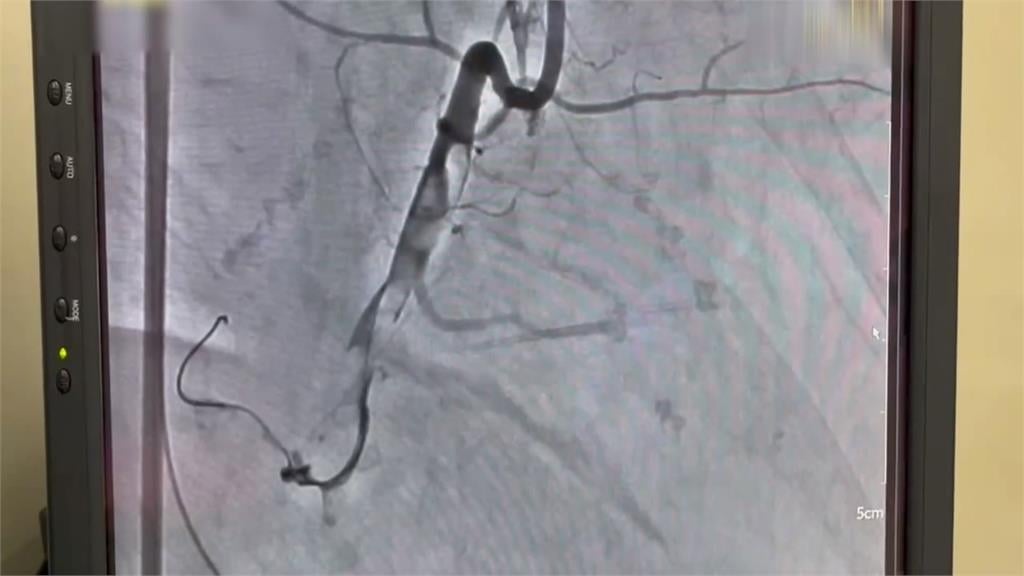

單靠CPR遠遠不足,送往醫院途中,救護人員為病患,進行10次AED電擊,到院時,心電圖顯示"致命性心律不整"。院方緊急裝上葉克膜,來維持病患的心跳與血液循環,爭取時間進行"心導管手術",打通被血栓堵住的血管,與死神搏鬥,成功搶回一命。根據統計,病人倒下6分鐘內如果即時獲得cpr急救,可以減少大腦損傷並且提高3倍存活率。不過每延遲一分鐘,存活率就會下降7%。如果在心跳停止時,"葉克膜"及時介入,存活率高達55%,像這名先生到院前就ohca,緊急實施"葉克膜心肺術"搶救,存活率有46%,倒下後的黃金幾分鐘,就可能替後續醫療爭取關鍵時間。